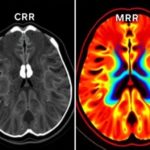

Когда речь заходит об остеопорозе, главный вопрос чаще всего звучит так: «Какой метод даст наиболее точную информацию о прочности кости и риске перелома?» Здесь ответ не один. КТ и МРТ решают разные задачи и дополняют друг друга. КТ прекрасно демонстрирует структуру кости: плотность костной ткани, наличие трещин, характер переломов и деформаций, а также может дать количественные показатели плотности кости. МРТ же рассказывает о состоянии костного мозга, наличии отеков и скрытых переломах, а также помогает оценить окружающие ткани — связки, мышцы и нервы — что важно при осложнениях и планировании лечения. В повседневной клинике эти две методики часто используются в связке: сначала рисунок общего состояния костей, затем подробное изучение особенностей позвоночника и соседних тканей, если появилась подозрительная симптоматика или есть необходимость уточнить диагноз.